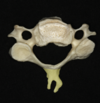

Atlas

Uncinate process

The uncinate process of the cervical spine is a hook-shaped process found bilaterally on the superolateral margin of the cervical vertebral bodies of C3-C7.

The uncinate processes are more anteriorly positioned in the upper cervical spine and more posteriorly location in the lower cervical spine.

Odontoid process

Superior articular facet for joint with occipital condyle

Facet joint

Lamina

Lateral mass

Spinous process

Transverse foramen